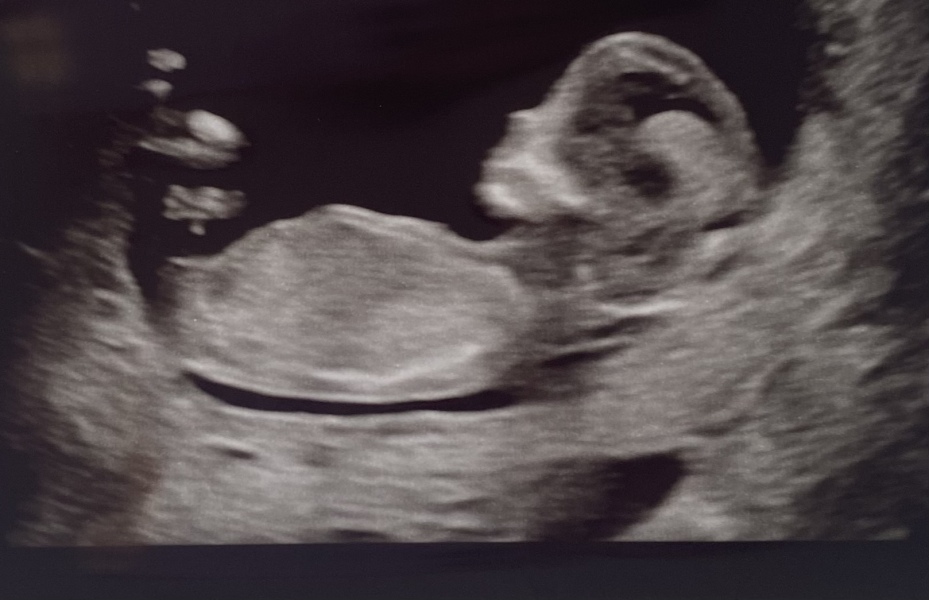

Hi could some guess mine please 13+2

12 week scan - nub/ skull theory

Boy or girl what’s your guess?💖💙